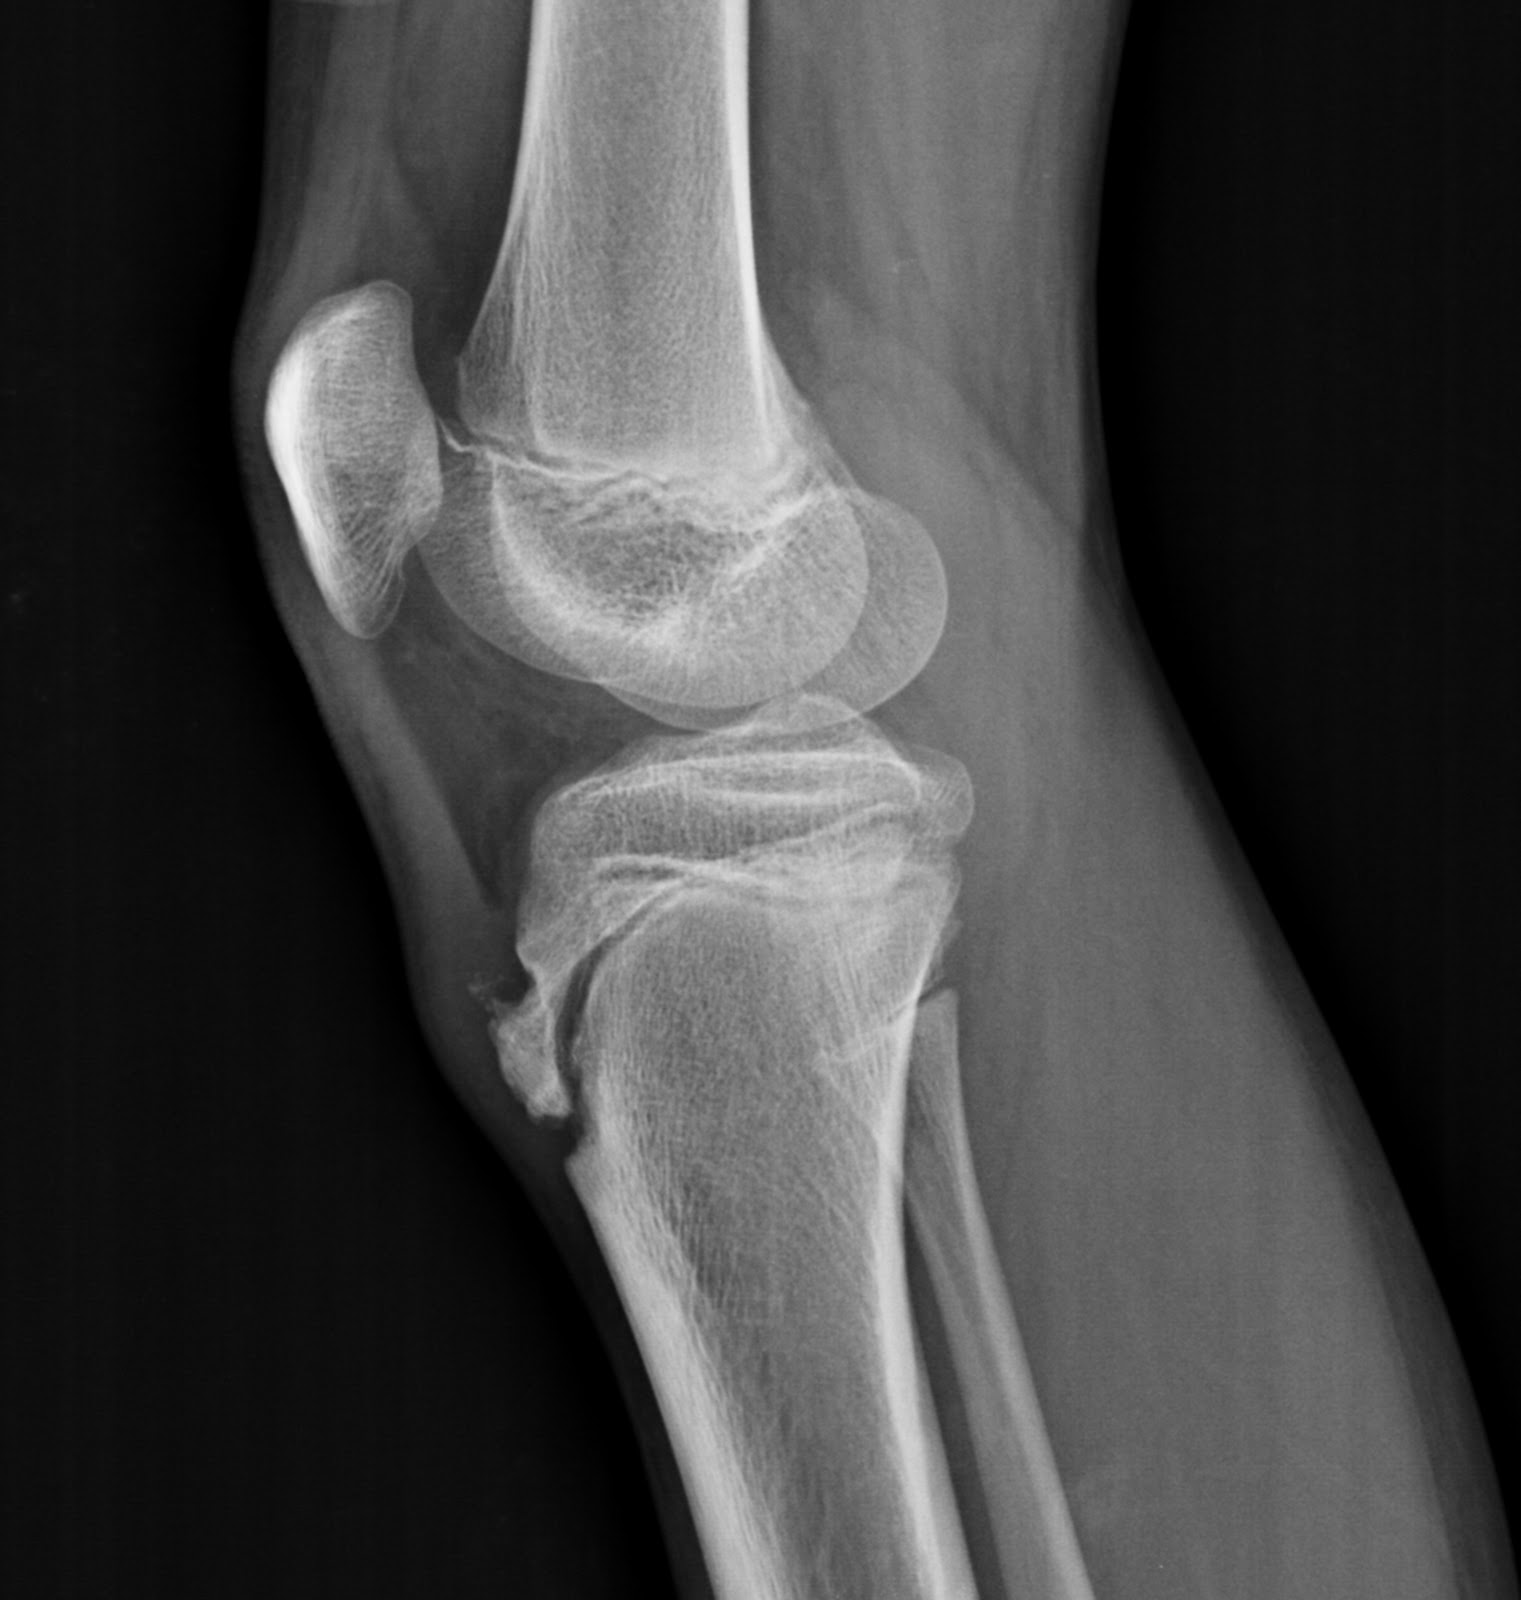

From thirdeye-radiologysite.blogspot.com

OsgoodSchlatter disease The Third Eye Radiology site What Is The Difference Between Osgood Schlatter S And Patellar Tendonitis The tibial tubercle (the tuberosity of the tibia) is the protuberance along the anterior aspect of the tibia, just distal to the anterior surfaces of the medial and lateral tibial condyles. It is an inflammation of the area just below the knee where the tendon from the kneecap (patellar. Osgood schlatter disease, also known as osteochondrosis or traction apophysitis of. What Is The Difference Between Osgood Schlatter S And Patellar Tendonitis.